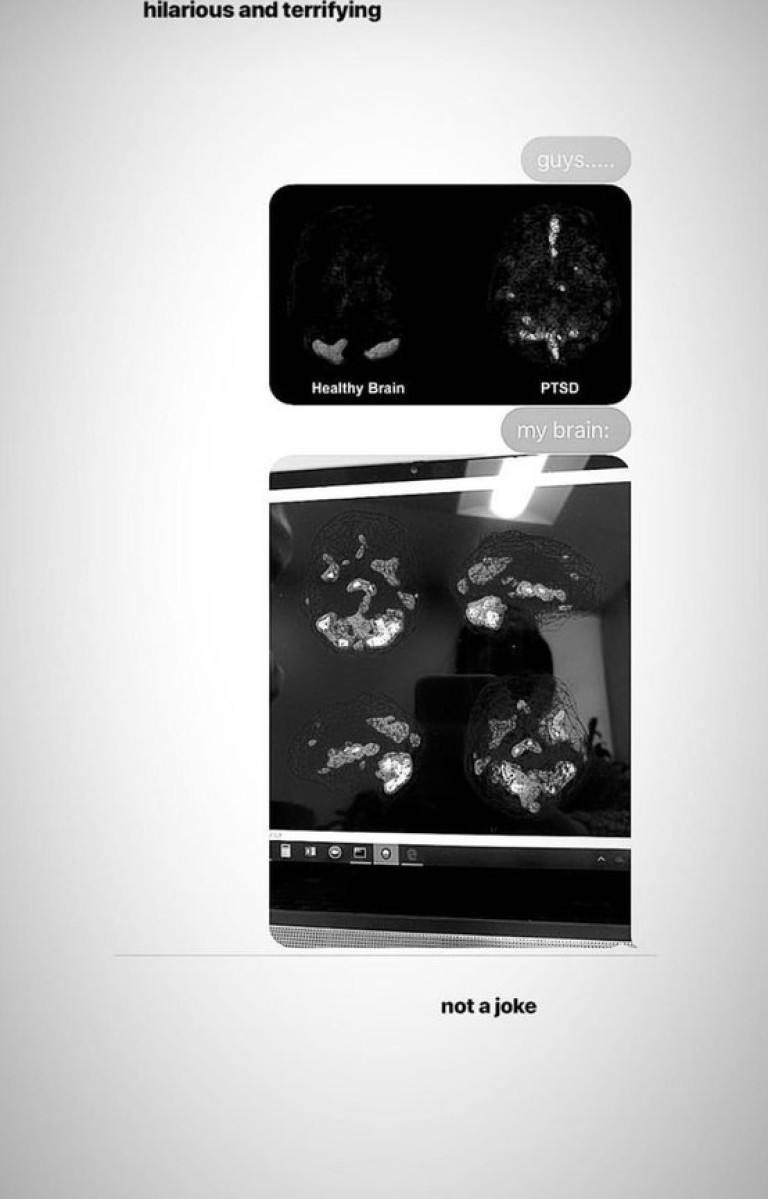

Посттравматично стресово разтройство е диагнозата, поставена на Гранде. Тя сподели снимки от направен скенер на главата и друг, на който се вижда "нормален мозък", допълвайки, че това е плашещо и въобще не е шега.

Снимка 418308

Според психиатри, силни травми, като тази някой да се взриви и да убие десетки на твой концерт, могат да доведат до трайни последствия в мозъка, за лечението на които са необходими медикаменти и специална терапия.

Симптомите, които се проявяват при това състояние, са тревожни мисли, депресия, безпокойство, натрапчиви спомени от травмиращия момент. Всички те са свързани с промени в мозъчни структури и невротрансмитери, които отговарят най-вече за страха и стреса. Именно те се забелязват на мозъчния скенер на изпълнителката.